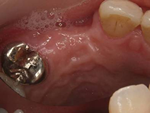

| 口腔内写真 | ![]() |

肉眼上では実際骨が歯茎で覆われているので骨の量が確認しにくいですが歯茎に厚みがないことが確認できるので骨質が少ないだろうと予想できます。